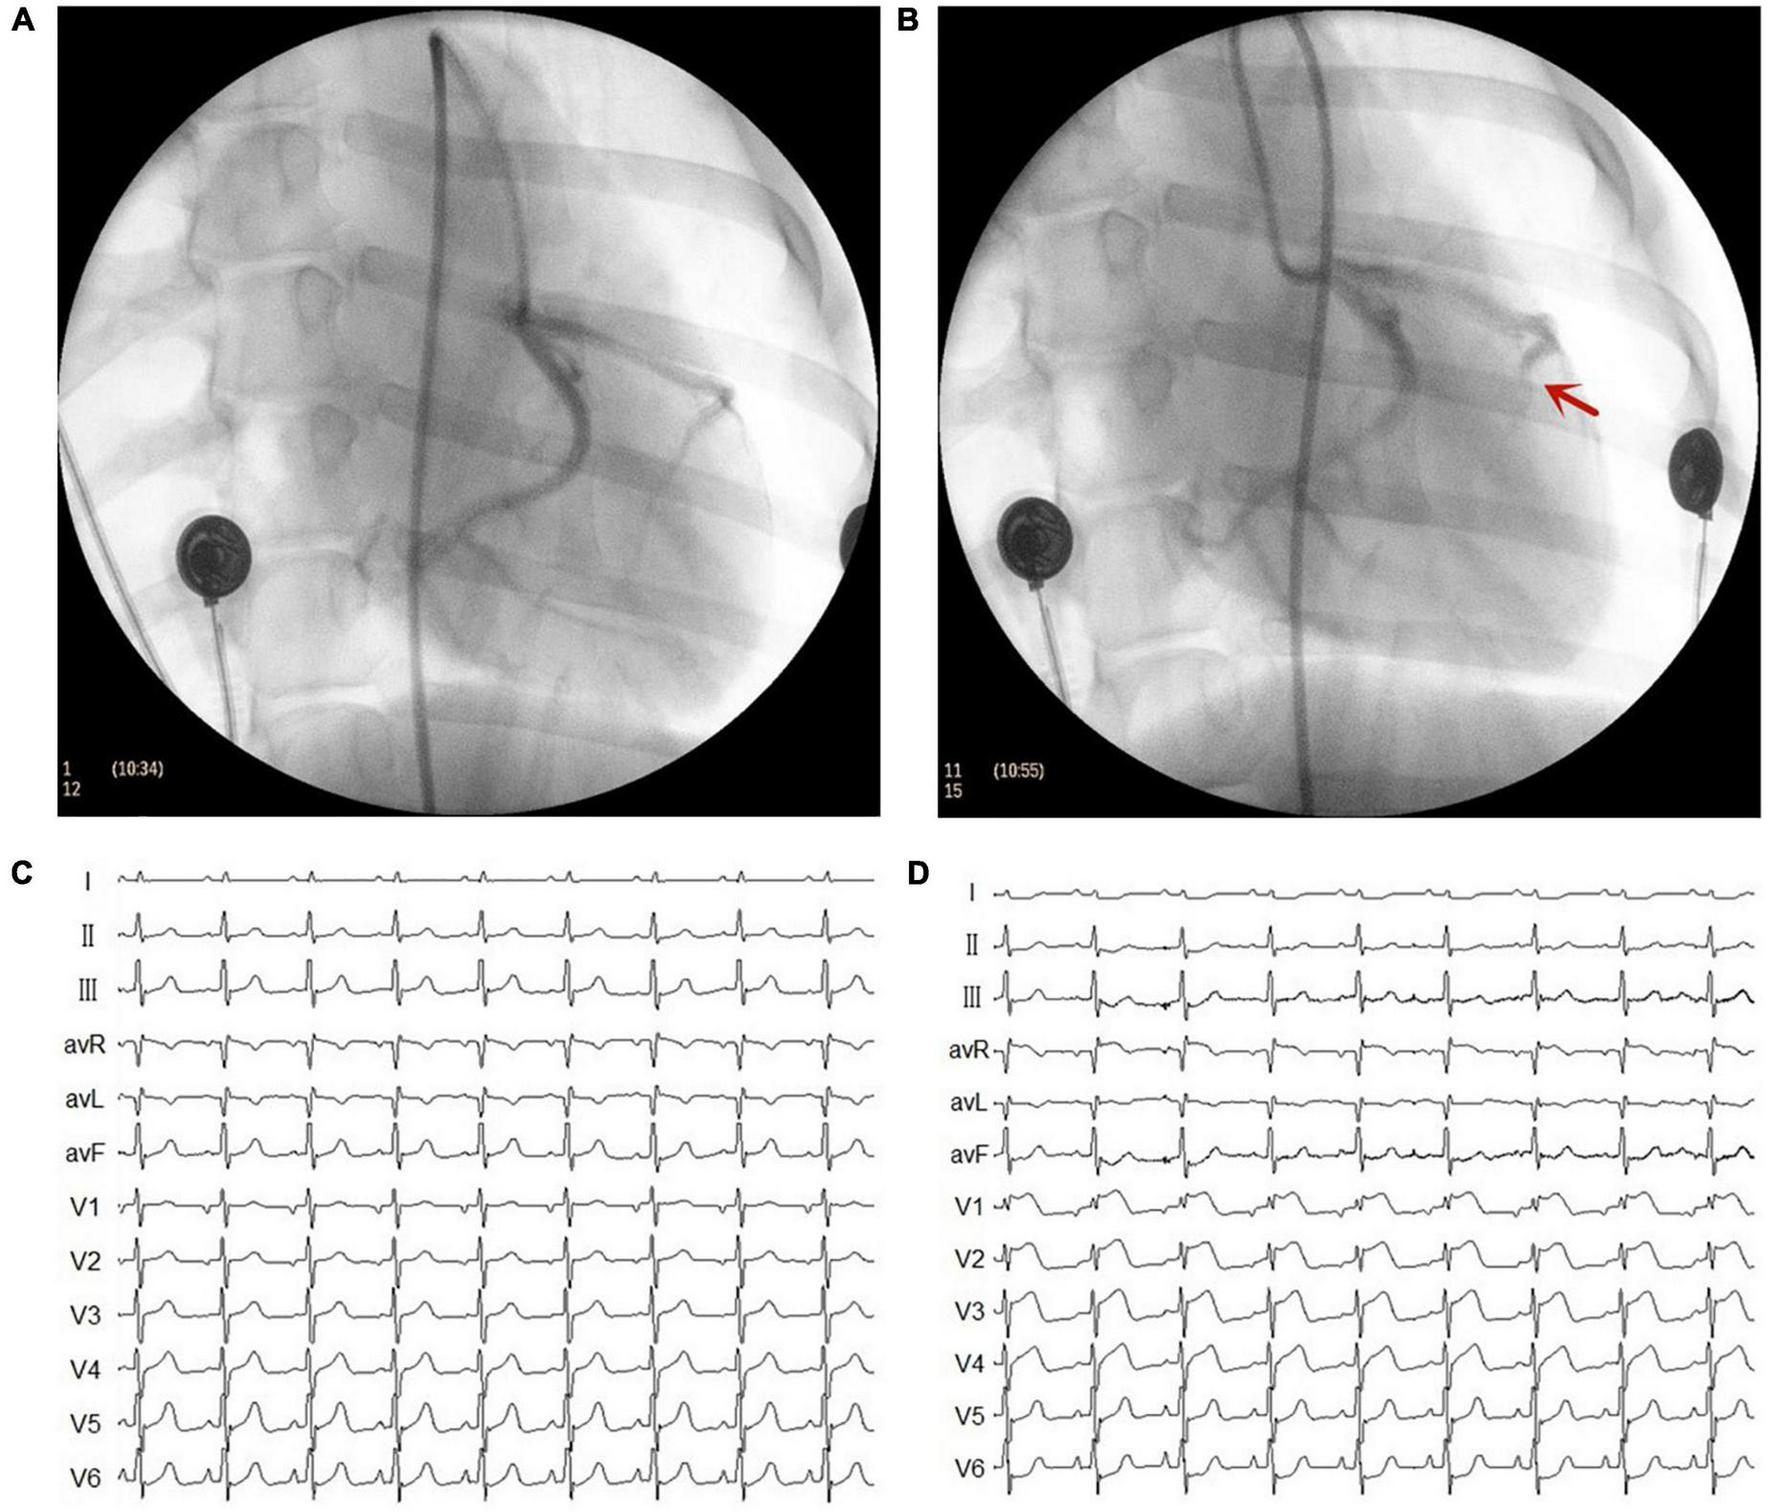

The MI model was established using catheter intervention. After administering stable anesthesia to all dogs, we injected 1000 U of heparin; then, we inserted hemostatic sheaths into their right femoral artery. Using X-ray fluoroscopy, a 5 F catheter was inserted into the left coronary artery to determine a coronary angiogram. Keeping the 5 F catheter positioned at the left anterior descending artery, a Radifocus SP catheter was delivered to the distal anterior descending artery through the 5 F catheter. A gelatin sponge with normal saline was injected into the distal anterior descending artery in 15 dogs. Notably, if the ST segment had no significant changes, the gelatin sponge with normal saline was reinjected. When the chest lead ST-segment was elevated, acute MI was achieved (Figure 1). The control group consisted of the other seven dogs injected with normal saline at the distal end of the anterior descending branch. Later, the animals were allowed to recover for 4 weeks. Figure 2 shows the time axis of procedures used in this study.

FIGURE 1

Representative images of X-ray and electrocardiogram (ECG) changes during the myocardial infarction (MI) model. (A) Left coronary artery arteriography before gelatin sponge injection. (B) Left coronary artery arteriography after gelatin sponge injection. Notably, the distal anterior descending artery had obvious stenosis. (C) ECG before gelatin sponge injection. (D) ECG after gelatin sponge injection, the chest lead ST segment was elevated.